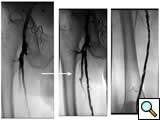

![]() |

Figure 1B: Following a day |

| Figure 1C: Angiogram shows restoration of limb perfusion. |

Case 1: An 84-year-old male with rest pain, who had undergone prior revascularization with covered stents, represents with recurrent rest pain. The prior stents had come close to the origin of the SFA and at that time there had been some narrowing. Exposure was provided by performing a cut down and patching the CFA-proximal SFA to the level of the stents, following which gentle thrombectomy was performed, and a wire passed down. The angiogram demonstrated a distal lesion at the adductor canal which contributed to the thrombosis (Figure 1A). The patient underwent a day of lysis, following which cryoablation was used to treat the distal lesion (Figure 1B) and completion angiogram showed restoration of limb perfusion (Figure 1C).

Case 2: A 74-year-old male with new onset severe claudication and threatened toes on the right side. An up-and-over wire was able to be advanced into the superficial femoral artery (but was totally occlusive). Cryoablation restored patency (Figure 2).

| Figure 2 |